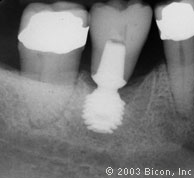

2. | 用一个6.0mm x 5.7mm短种植体支撑一个一体化基台冠修复左下颌第一磨牙。注意下齿槽神经管的水平。 |